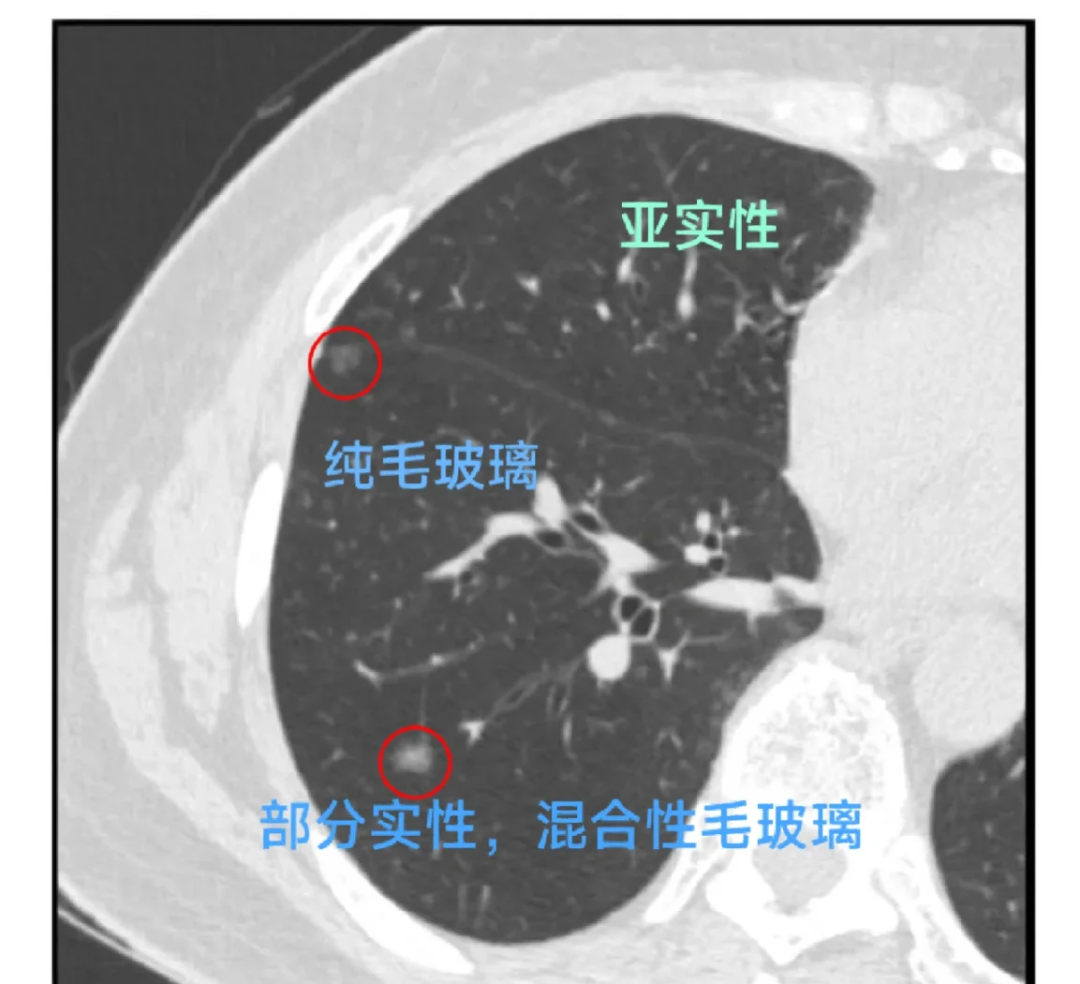

结节什么性质?(实性 / 磨玻璃 / 部分实性)

磨玻璃或部分实性结节 ≥ 6mm

建议长期随访,可最长跟到 5 年

磨玻璃结节中实性成分明显增多,随访中持续长大

同时,越来越多的研究表明: 对一些小的、纯磨玻璃结节,可以在严格随访下观察多年, 而不是一概手术,以避免过度治疗。

先对号入座,看自己属于哪一类结节大小?性质(纯磨玻璃 / 部分实性 / 实性)?